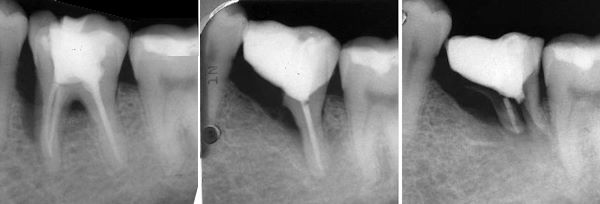

links: Der abgespreizte palatinale Höcker

Mitte: Höcker entfernt, Wurzelkanal aufbereitet (2 Kanäle).

Der Kanalinhalt war fötid

rechts: Wurzelfüllung apikal (2 Kanäle) und koronal

(1 Kanal und Bett für den Titanstift).

links: Der palatinale Höcker, 11 mm lang. 2 mm waren angewachsen.

Mitte: Titanstift zementiert, die Matrize reicht bis 3 mm unter das Zahnfleisch.

rechts: Der fertige Aufbau.

Granulom: Es war schmerzfrei, entliess aber ständig ein klares Sekret aus einem Seitenkanal von distal. Die Wurzelfüllung (AH Plus und Guttastifte) wurde im nassen Kanal gemacht.

"aus gegebenem Anlass melde ich mich nun nach 30 Monaten wieder. Was soll ich sagen? Die nach 15 Monaten beschriebenen kleinen Beschwerden sind mittlerweile so gut wie ganz weg, ein deutscher Zahnarzt fertigte kürzlich eine Panoramaaufnahme an und das sieht alles richtig gut aus."